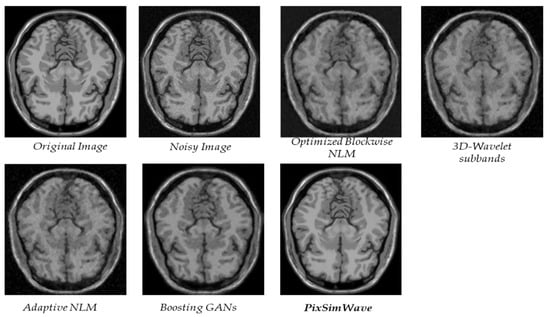

4.1. Visual Result of PixSimWave Algorithm

4.3. Real Clinical MRI